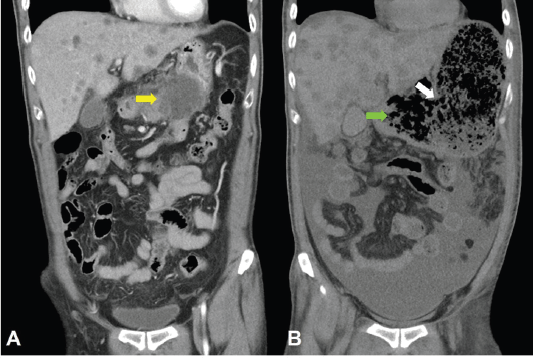

Unfortunately, a catastrophic event did happen 2 days after finishing the first course of chemotherapy. The patient experienced sudden onset of intolerable abdomen pain with hypoactive bowel sounds, muscle guarding, and definitely apparent rebounding pain. An emergent non-contrast CT scan gave a picture of distended stomach fully filled with foods, irregular mottled gas collections between stomach and duodenum, ascites accumulation, and free air in the abdomen cavity, leading to an impression of gastrointestinal tract perforation with the perforation site clearly seen (Figures 6–8). In comparison with CT scan performed at initial diagnosis, it seemed that a severe necrotising tumour lysis induced by chemotherapy, morphologically resembling emphysematous pancreatitis [14–16], could explain the whole scenario logically.

Figure 7. CT scan of the abdomen, coronal view. A. June 8, 2019. Yellow arrow: the huge gastric tumour. B. July 3, 2019. White arrow: gastric perforation site. Green arrow: Necrotising tumour lysis simulating emphysematous pancreatitis.

Figure 8. CT scan of the abdomen, coronal view. A. June 8, 2019. Yellow arrow: the huge gastric tumour. B. July 3, 2019. Green arrow: Necrotising tumour lysis simulating emphysematous pancreatitis.